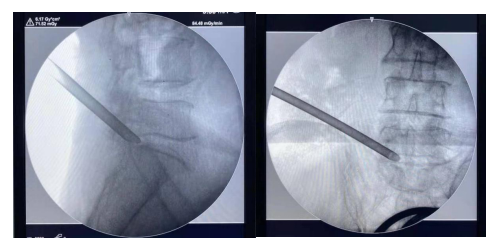

三、椎間盤微創介入技術,如:等離子消融、射頻熱凝術、臭氧髓核溶解術治療頸腰椎間盤突出癥、椎間盤盤源性疼痛。

五、脊柱椎間孔鏡技術治療腰椎間盤突出癥。

六、關節鏡技術治療肩關節疼痛及肩袖損傷、膝關節滑膜炎、半月板損傷、游離體形成、腘窩囊腫等。